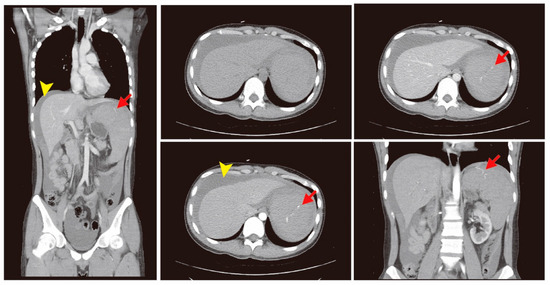

The bedside ultrasound revealed much ascites, which confirmed the emergency abdominal contrast enhanced computed tomography (CT) in the previous transfer hospital and showed splenomegaly and splenic rupture with hemoperitoneum (Figure 1). Adequate fluid resuscitation and emergency blood transfusion were performed to correct the hypovolemic shock status. Transamine (1000 mg) and vitamin K1 (10 mg) were administered to control the bleeding. The opioid agent morphine (10 mg) was used to control progressive abdominal pain. An emergency transcatheter arterial embolization was performed to control persistent splenic hemorrhage (Figure 2).

Figure 1.

The abdominal contrast enhanced computed tomography (CT) showed splenomegaly and a splenic rupture (red arrow) with hemoperitoneum (yellow arrow head).